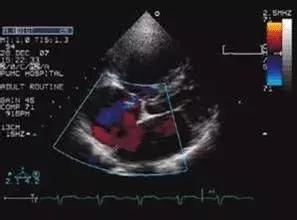

心脏彩超

彩超不是大家以为的电视机黑白与彩色的概念,彩超是用来编码,用技术显示出血管里面流动血液的编码。红色并不代表动脉,蓝色也不代表静脉,而代表血流的方向,流向探头的是红色的血流,背离探头的称为蓝色,血流速度快的,可以看到五彩的颜色,通常能诊断很多疾病,比如心脏瓣膜狭窄,把血流加上去会看到五彩镶嵌的血流冲过来有阻挡。